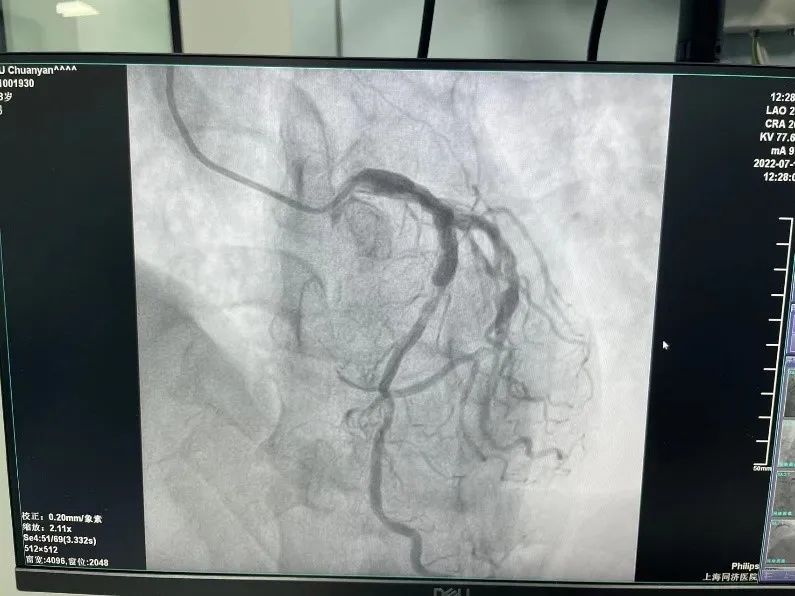

在球囊扩张开通闭塞血管的同时,可以看到患者的前降支非常发达,近段弥漫的瘤样扩张、血管钙化合并中段重度狭窄。使用血管内超声可以看到患者狭窄存在360°钙化。这样的病变是心血管内科介入医生最为头痛的。重度钙化可导致支架通过困难、支架膨胀不良等情况,容易发生支架脱载、急性支架内血栓、围术期心肌梗死等并发症。

支架植入前